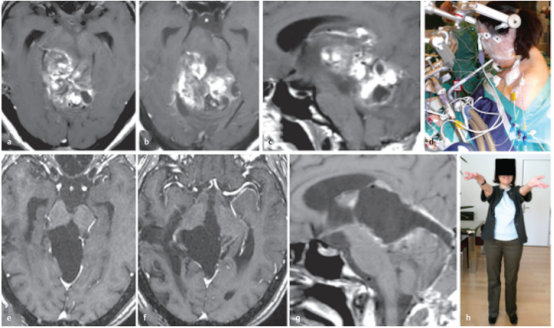

术前:术前轴位(a,b)和矢状面(c)MRI显示,较大肿瘤,从中脑两侧延伸到丘脑、脑桥和小脑。

术中:半坐位,广泛性肿瘤切除术

术后:轴位(e,f)和矢状位(g)T1加权增强MRI检查显示,外生毛细胞星形细胞瘤被成功切除。病人没有出现额外的神经功能缺损,随后的病程平安无事。h,显示在根治性肿瘤切除术后10年的随访中,患者的病情持续良好,没有复发。

This 28-year-old woman had progressive gait ataxia and slight diplopia. A midbrain tectal tumor was diagnosed in her home country 4 years before her presentation to our clinic. The patient underwent 2 surgical explorations in other hospitals, and each time no more than a tumor biopsy was undertaken. Histopathologically, a pilocytic astrocytoma was diagnosed. As the tumor continued proliferating, the patient was advised elsewhere to undergo radiotherapy and thereafter chemotherapy with temozolomide for a period of 12 months. When the patient presented to our institute for the first time, the tumor had reached a very large size, extending from the midbrain into the thalamus, pons, and cerebellum bilaterally as shown on preoperative axial (a,b) and sagittal (c) magnetic resonance images (MRIs). As none of the previous therapies achieved efficient tumor control, we offered the patient extensive tumor resection. (d) She agreed and underwent the procedure in the semisitting position. Complete removal of this exophytic pilocytic astrocytoma World Health Organization grade I tumor was successful as documented on postoperative axial (e,f) and sagittal (g) T1-weighted contrast-enhanced MRIs. The patient experienced no additional neurologic deficits, and her subsequent course was uneventful. (h) At 10-year follow-up after radical tumor removal, the patient continued to do well and remained recurrence-free.